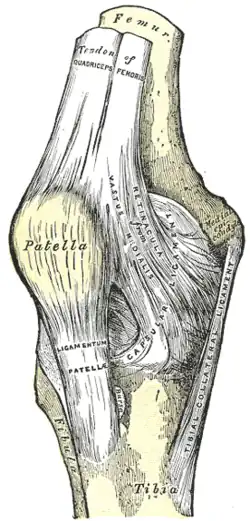

Kniescheibe

Die Kniescheibe ist dreieckig und an ihrer Vorderfläche etwas nach außen gewölbt. Sie ist als Sesambein in die Ansatzsehne des vierköpfigen Oberschenkelmuskels (Musculus quadriceps femoris) eingelagert, der sie von oben kommend einbettet. Von ihrer unteren Spitze (Apex patellae) entspringen die Fasern des Kniescheibenbandes (Ligamentum patellae). Auf der Hinterseite der Kniescheibe (Facies articularis patellaris) befindet sich ein First, der die Gelenkflächen in zwei Facetten unterteilt. Ihre Knorpelschicht ist etwa sechs Millimeter dick.

Bei gebeugtem Knie liegt die Kniescheibe fest in der Furche kurz oberhalb des Gelenkspaltes zwischen Oberschenkelknochen und Schienbein, bei gestrecktem Bein weiter oberhalb. Deshalb lässt sie sich zwar bei Streckstellung und entspannter Muskulatur ein wenig nach rechts und links verschieben, jedoch nicht in Beugestellung.

Hauptaufgabe der Kniescheibe ist die Verlängerung des Hebelarms und somit des Drehmoments des Quadrizeps, da sie den Abstand seiner Kraftwirkungslinie vom Bewegungszentrum des Kniegelenks erhöht. Zudem dient sie der Führung der Sehne und verringert den Widerstand der Gleitbewegung der Sehne über den Knochen.

Kniescheibengelenk

Das Kniescheibengelenk (Articulatio femoropatellaris) ist das Gelenk zwischen Oberschenkelknochen und Kniescheibe. Dabei stehen sich die mit hyalinem Knorpel überzogene Gelenkfläche auf der Rückseite der Kniescheibe (Facies articularis patellae) und die auf der Vorderseite des Oberschenkelknochens (Facies patellaris femoris) gegenüber. Die Kniescheibe gleitet bei Beugung und Streckung in der für sie vorgesehenen Rinne etwa fünf bis zehn Millimeter über den Oberschenkelknochen, der Eintritt in die Rinne erfolgt bei ungefähr 30° Beugung. Diese Gelenkform wird auch als Schlittengelenk (Articulatio delabens) bezeichnet.

Bänder

Vordere Bandsicherung

Das fünf bis sechs Millimeter dicke Kniescheibenband (Ligamentum patellae, „Patellasehne“) ist Teil der Gelenkkapsel und zieht als Fortsetzung der Quadrizepssehne vom unteren Rand der Kniescheibe bis zur vorderen Aufrauung des Schienbeines, der Schienbeinbeule (Tuberositas tibiae),[13] wo es großflächig ansetzt. Mittig und seitlich zur Kniescheibe und zum Kniescheibenband verläuft ein weiteres Band (Retinaculum patellae). Dieses teilt sich in einen mittleren Anteil (Retinaculum patellae mediale), der aus dem zur Mitte gerichteten breiten Oberschenkelmuskel (Musculus vastus medialis) entsteht und einen seitlichen Anteil (Retinaculum patellae laterale), der sich aus dem seitlichen breiten Oberschenkelmuskel (Musculus vastus lateralis) bildet. Sie sind Teil der äußeren Schicht der Gelenkkapsel.

Strecker